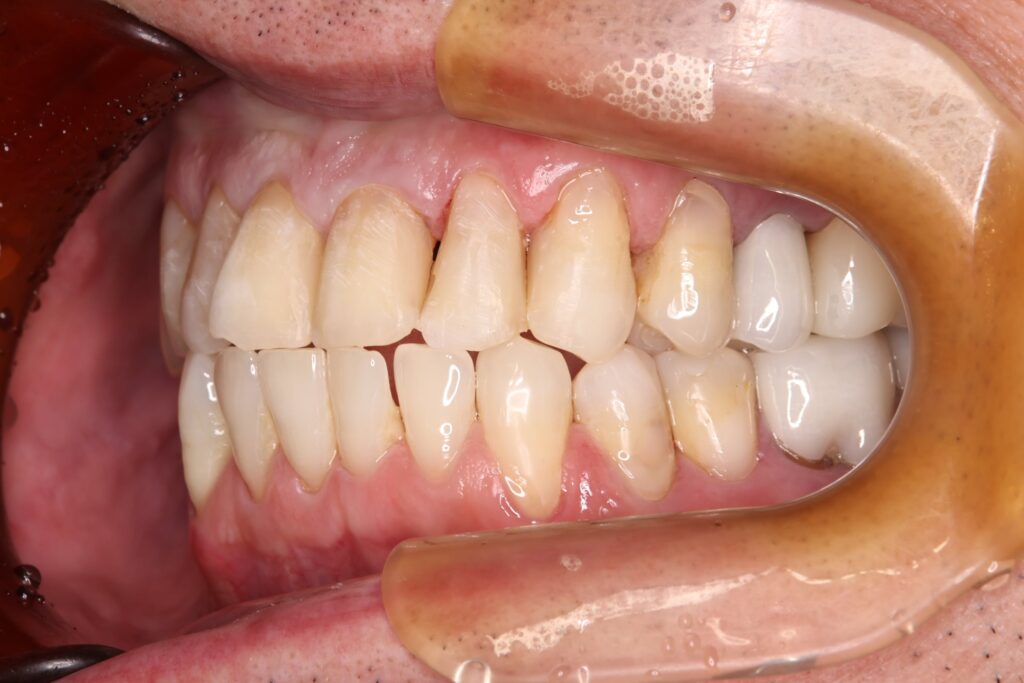

治療結果

銀歯をすべてセラミックへ置き換え、あわせてホワイトニングを行ったことで、口腔内全体が明るく清潔感のあるお口元になりました。また審美的な向上が得られただけでなく、プラーク(細菌)が付着しにくい環境を整えることができた点も大きな成果です。

また、痛みや違和感の原因となっていた部位についても適切な処置を行ったことで、現在は違和感なく、安心して噛める状態が維持されています。

機能面と審美面の両面において、良好な治療結果が得られました。